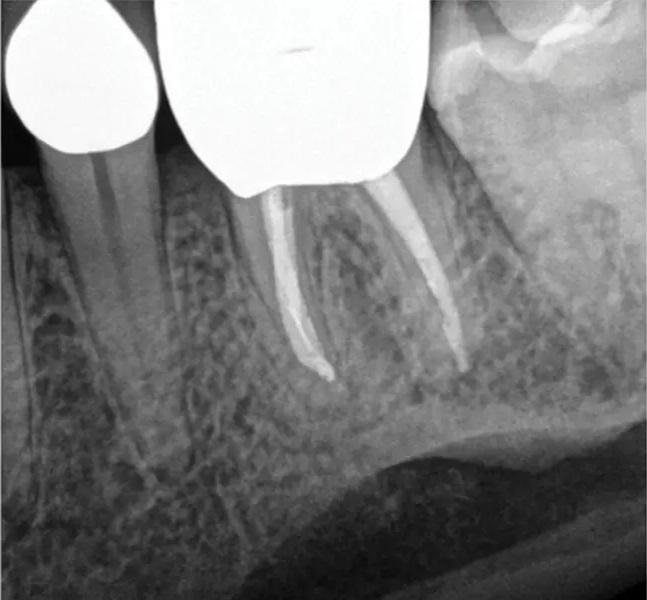

Фото 1. Клинический случай 1. Периапикальная рентгенограмма, демонстрирующая периапикальную патологию, связанную с зубом 36, обусловленную неустраненными осложнениями первичного нехирургического эндодонтического лечения, включая отлом инструмента и коронковую негерметичность. Неустраненные осложнения могут приводить к неудаче эндодонтического лечения и усложнять проведение нехирургического повторного лечения, делая его исходы менее предсказуемыми.